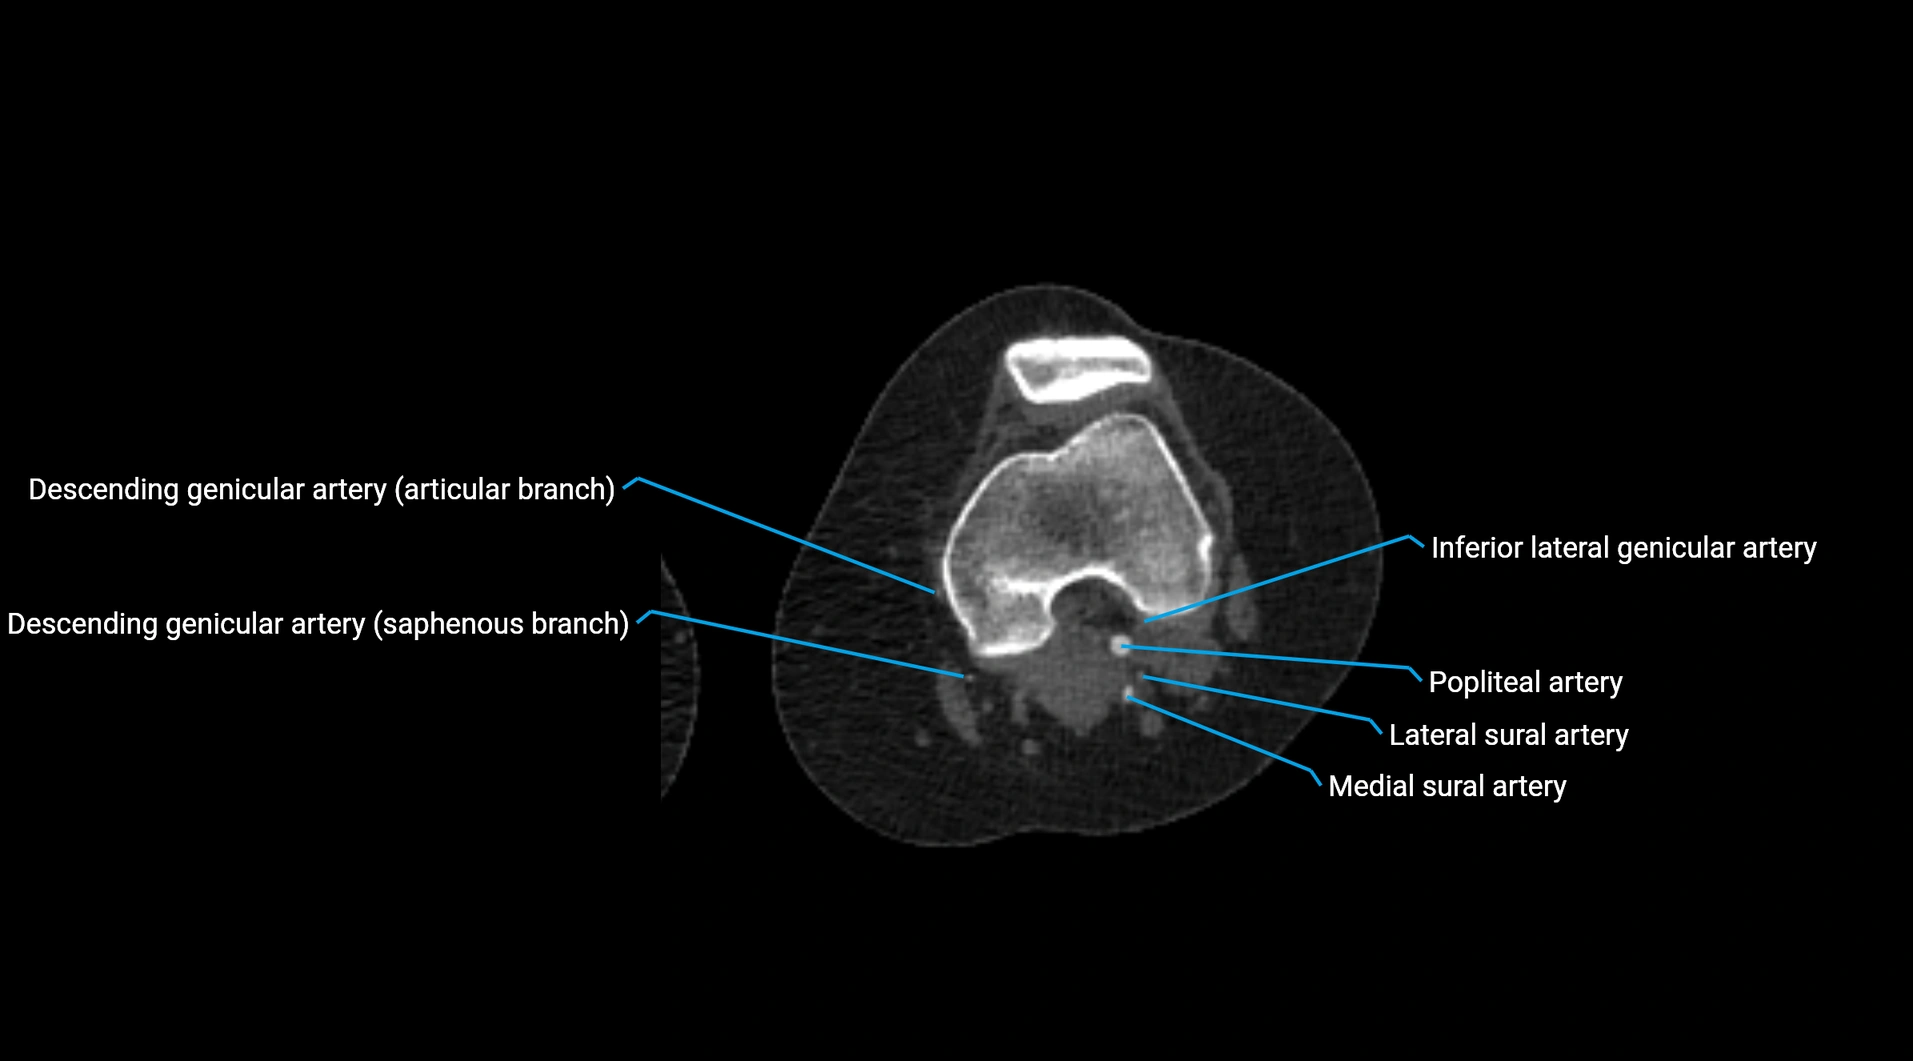

CT Appearance

Non-contrast CT:

• Appears as a tubular soft tissue structure anterior to vertebral bodies

• Calcified atherosclerotic plaques appear as hyperdense foci along the wall

• Useful for screening abdominal aortic aneurysm (AAA) size and mural calcification

Contrast-enhanced CT (CTA):

• Gold standard for abdominal aortic imaging

• Provides excellent detail of lumen, wall, aneurysm, thrombus, and branch vessels

• Multiplanar and 3D reconstructions help in aneurysm measurement, stent graft planning, and dissection evaluation

• Detects acute rupture, traumatic injury, or occlusion with high sensitivity